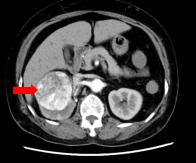

肾癌(Renal cell carcinoma,RCC),别名肾细胞癌、肾腺癌,是起源于肾小管上皮细胞的一组恶性肿瘤,是成年人常见的肾脏恶性肿瘤。好发年龄为60~70岁,男女比例为2:1,双侧发生占1%。在世界范围内,肾癌的发病率约占成人恶性肿瘤的2%~3%,其分布具有明显的地域差异,北美、西欧等西方发达国家发病率最高,而非洲及亚洲等发展中国家发病率最低。其临床上多以无症状性血尿为首发症状,还有腰痛、腹部包块,其他表现包括体重下降、贫血、发热等。少数患者还会出现副肿瘤综合征的表现,如红细胞增多症高钙血症、高血压等。[3][2][4]

肾癌的常见病理类型包括透明细胞肾细胞癌、乳头状肾细胞癌、嫌色细胞肾细胞癌等。[2]肿瘤可破坏全部肾组织,并可侵犯邻近的脂肪、肌肉组织、血管、淋巴管等。肿瘤穿透假包膜后可经血液和淋巴转移。肾癌容易向静脉内扩散,形成癌栓,可延伸进入肾静脉、下腔静脉及右心房。远处转移的常见部位包括肺、脑、骨、肝等。[6]肾癌采用综合治疗方式,主要包括手术治疗、内科治疗(细胞因子治疗、靶向治疗、化学药物治疗等)以及介入治疗。[5][2]